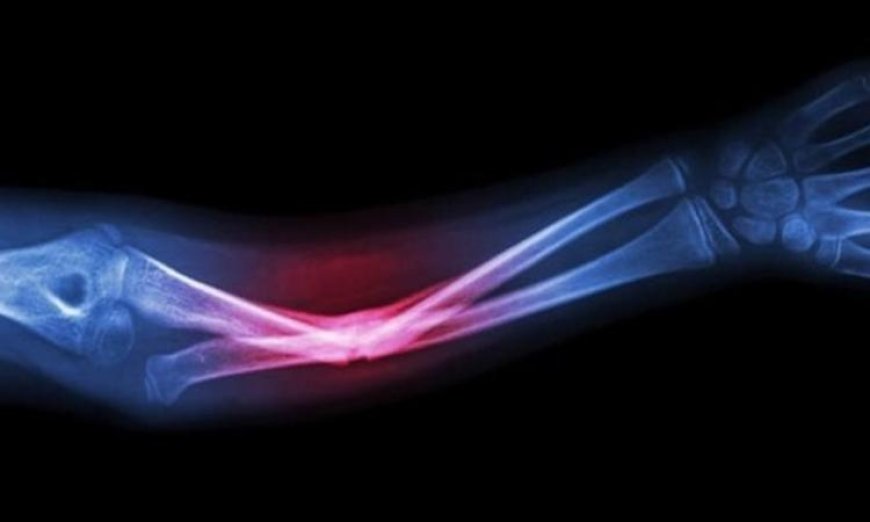

تشير الدراسات إلى أن هذه المادة الحيوية تتداخل بأمان مع جسم المريض، مما يساعد في تحفيز العمليات الشفائية الطبيعية ويشكل قاعدة لنمو عظام جديدة. إن هذا الابتكار قد يُعزز فعالية العلاجات المستخدمة في طب الأسنان وجراحة الوجه والفكين، إضافة إلى معالجة الإصابات العظمية.